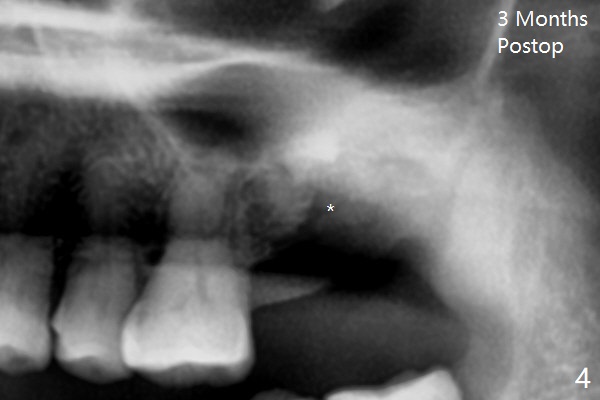

A 61-year-old woman requests #15 implant post ones at #2 and 6 because of pain in mastication (Fig.1). Examination shows that the tooth #16 has advanced periodontitis with mesial bone loss (Fig.1 *). It appears that there is insufficient bone for #15 implant. Bone graft seems necessary at #16 after extraction. There is severe hemorrhage post extraction. Osteogen plug is inserted for hemostasis prior to placement of allograft (Fig.2 *). The socket opening is covered with 12x12 mm Amnion-Chorion Membrane and 5-0 Polysyn. The socket seems to heal 9 days postop (Fig.3). The bone graft in the socket of #16 three months postop (Fig.4 *) will support an implant to be placed at #15 distal (Fig.5 *).